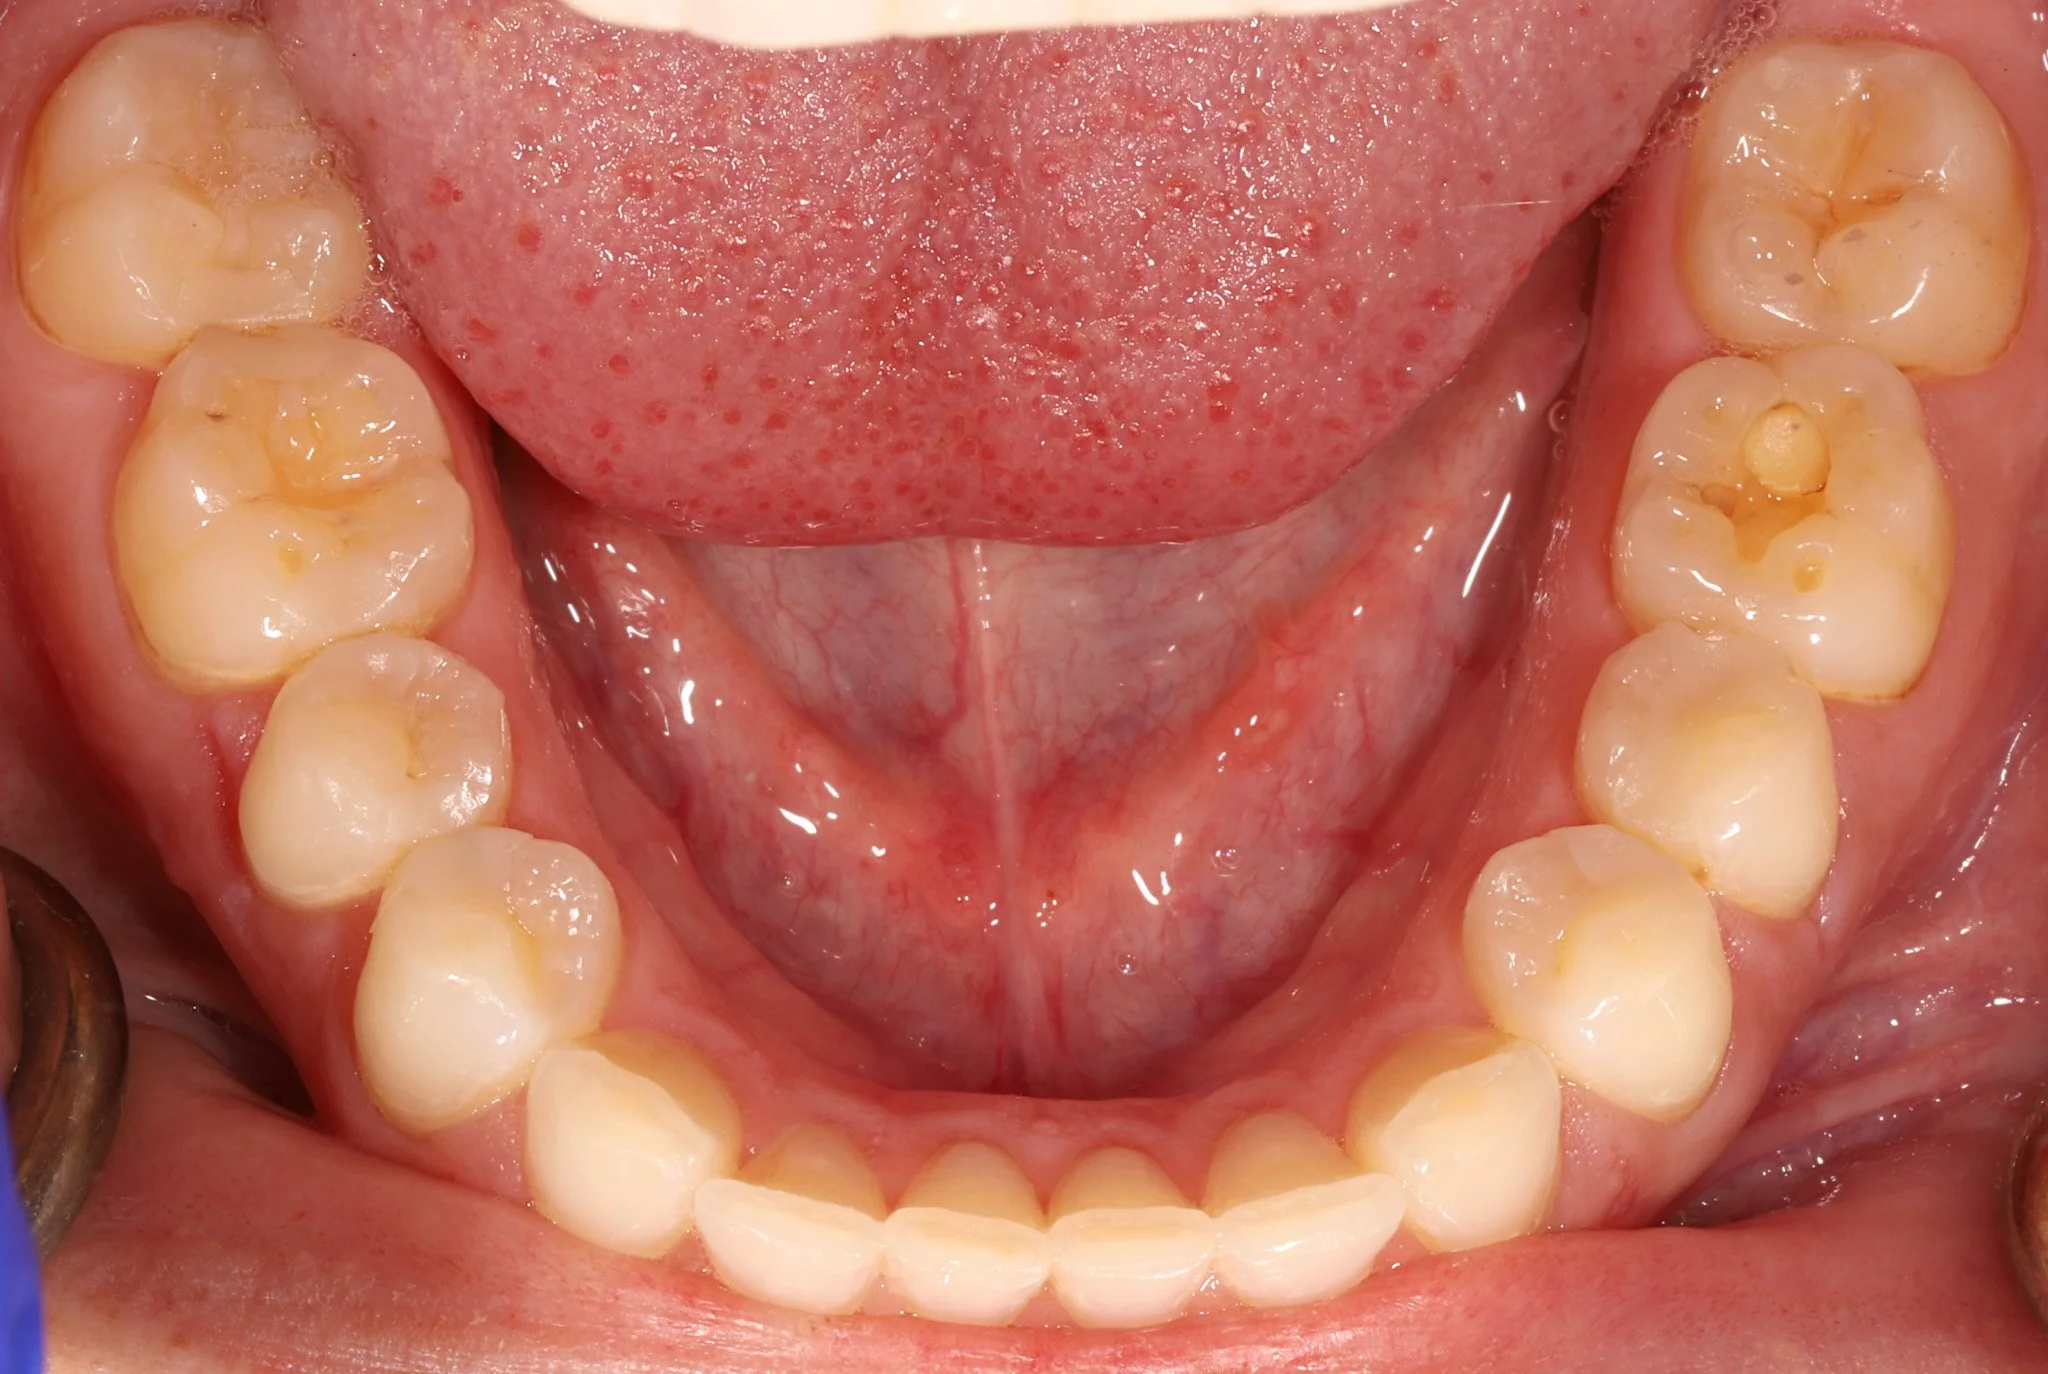

Open mouth displaying upper and lower molars with multiple cavities and decay.

Before: Silver fillings, leakage, cracks, decay

Open mouth showing upper and lower teeth with healthy gums and tongue

After: Combination of bonded porcelain and composite to restore teeth